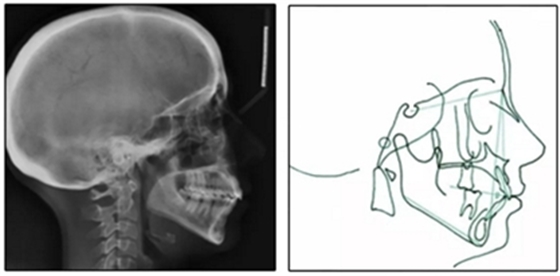

患者是一名39歲的白人婦女,病史不明。她主訴是她的右側(cè)顳下關(guān)節(jié)有不適癥狀,并希望改善她的笑容。她有一個(gè)對(duì)稱的臉型和一個(gè)II類2分類的微笑。她的側(cè)貌是凸的,90°的鼻唇角和骨性下頜骨發(fā)育不足??趦?nèi),上頜中線與面部重合,但下頜中線向右側(cè)偏移5mm;存在6mm的深覆蓋。她的兩側(cè)都是I類磨牙關(guān)系,左側(cè)是I類尖牙關(guān)系,右側(cè)是完全的II類尖牙關(guān)系。下頜右側(cè)第二前磨牙先天性缺失(圖1和圖2)。最初的全景片顯示了足夠的骨質(zhì)水平和全部的第三磨牙(圖3)。治療前的頭影測(cè)量片片和相應(yīng)的頭影測(cè)量圖(圖3)證實(shí)ANB為7°,Wits評(píng)估為6 mm的骨性II類錯(cuò)合(表)。上頜切牙相對(duì)與面部和顱底的位置很好。下頜切牙前傾。診斷為II類2分類錯(cuò)合畸形,伴有骨性下頜發(fā)育不足,右側(cè)顳下頜關(guān)節(jié)癥狀,下頜中線向右側(cè)偏移5mm,先天性右下第二前磨牙缺失。

圖3. 治療前頭影側(cè)位片,頭影測(cè)量描跡圖和全口X光片